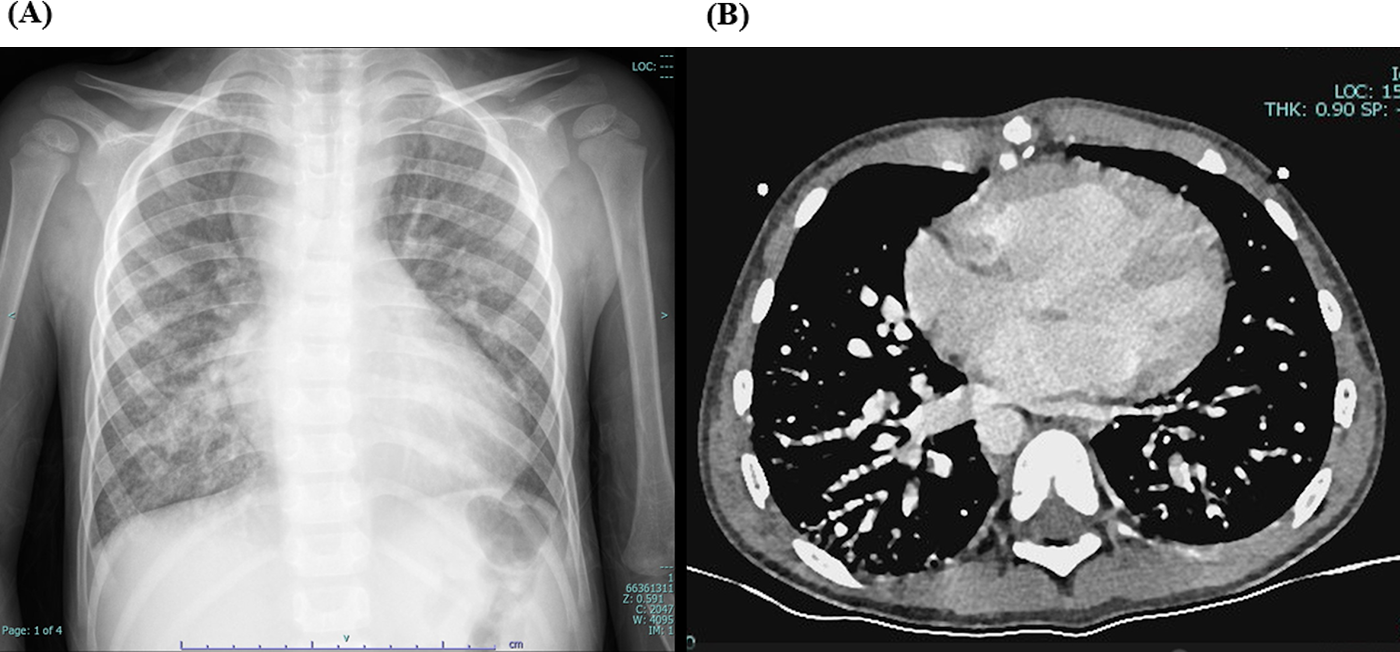

Laboratory tests showed hemoglobin of 225 g/L and hematocrit of 73.3%. Arterial blood gas analysis revealed a partial pressure of oxygen (PO₂) of 30.7 mmHg and oxygen saturation (SO₂) of 58.1%. Chest X-ray showed cardiomegaly (cardiothoracic ratio 0.6) and increased pulmonary markings (Figure 1A). Echocardiography revealed absence of antegrade pulmonary artery flow; a 23 mm VSD located beneath the pulmonary valve with bidirectional shunting; a 23 mm ASD with bidirectional shunt; and a patent Glenn anastomosis. Contrast-enhanced CT showed ASD and VSD, absence of the pulmonary valve and main pulmonary artery, confluence of the right and left pulmonary arteries, reduced pulmonary blood flow, and extensive PAVMs in both lungs—most prominent in the lower lobes (Figure 1B). The measured McGoon ratio was 1.857. Cardiac catheterization confirmed absence of antegrade pulmonary artery flow, with well-developed right and left pulmonary arteries. The distal pulmonary arteries and pulmonary venous branches were markedly dilated, with some showing a granular or “string-of-beads” appearance (Figure 2). Pulmonary circulation time was significantly shortened, indicating substantial right-to-left intrapulmonary shunting, consistent with diffuse PAVMs. The lower lobes were most severely involved. Pulmonary artery pressure was 17/9/13 mmHg.

Figure 1

(A) preoperative chest X-ray showing increased pulmonary markings. (B) Preoperative contrast-enhanced cardiac CT demonstrating simultaneous opacification of pulmonary arteries and veins, with a beaded appearance of the distal pulmonary arteries, more prominent in both lower lobes, consistent with diffuse pulmonary arteriovenous malformations (PAVMs).